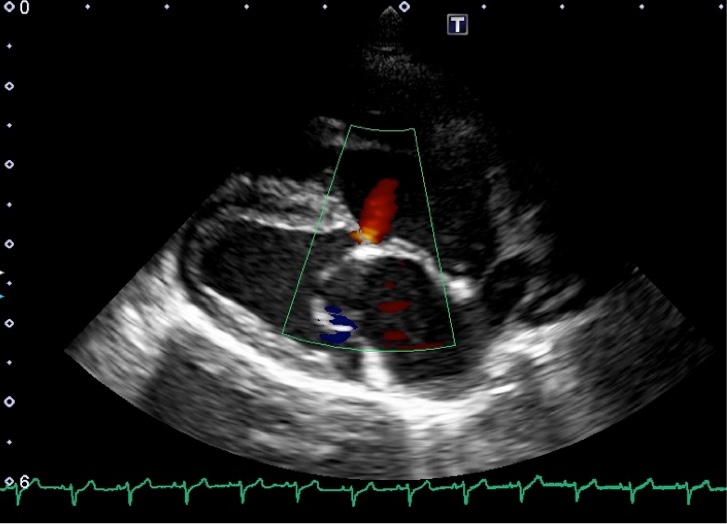

・心臓超音波検査